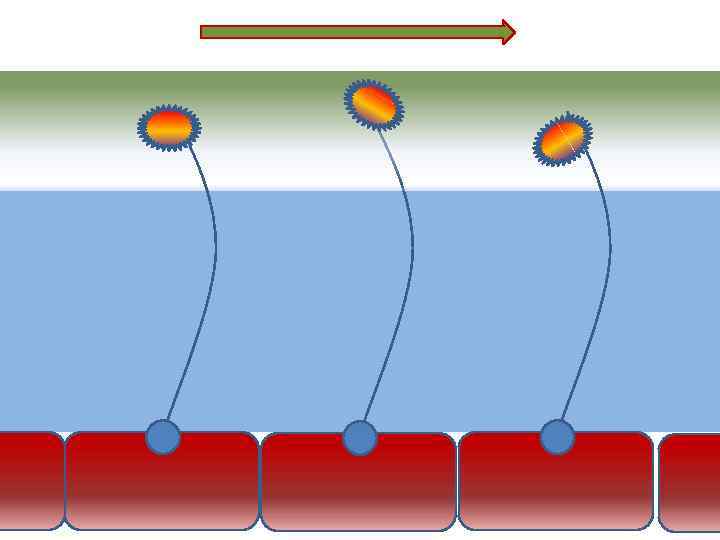

Оптимальное увлажнение Достаточная продукция слизи Хороший транспорт Экономит энергию и воду Защитная функция

Оптимальное увлажнение Достаточная продукция слизи Хороший транспорт Экономит энергию и воду Защитная функция

Механизм защиты легкого Слизь (зеленый цвет) нейтрализует и связывает патогенную флору(синий цвет) Слизь – это барьер между клетками и патогенной флорой Слизь – это транспортное средство

Механизм защиты легкого Слизь (зеленый цвет) нейтрализует и связывает патогенную флору(синий цвет) Слизь – это барьер между клетками и патогенной флорой Слизь – это транспортное средство

Нормальное состояние слизистого бронхиального секрета возможно только при 100% относительной влажности воздуха

Нормальное состояние слизистого бронхиального секрета возможно только при 100% относительной влажности воздуха

Плохое увлажнение • Вязкая слизь - потеря ресничек • Высушивание слизистой смерть клеток • Высушивание слизи в бронхиолах-ателектазы • Затраты энергии на согревание воздуха • Затраты воды на увлажнение

Плохое увлажнение • Вязкая слизь - потеря ресничек • Высушивание слизистой смерть клеток • Высушивание слизи в бронхиолах-ателектазы • Затраты энергии на согревание воздуха • Затраты воды на увлажнение